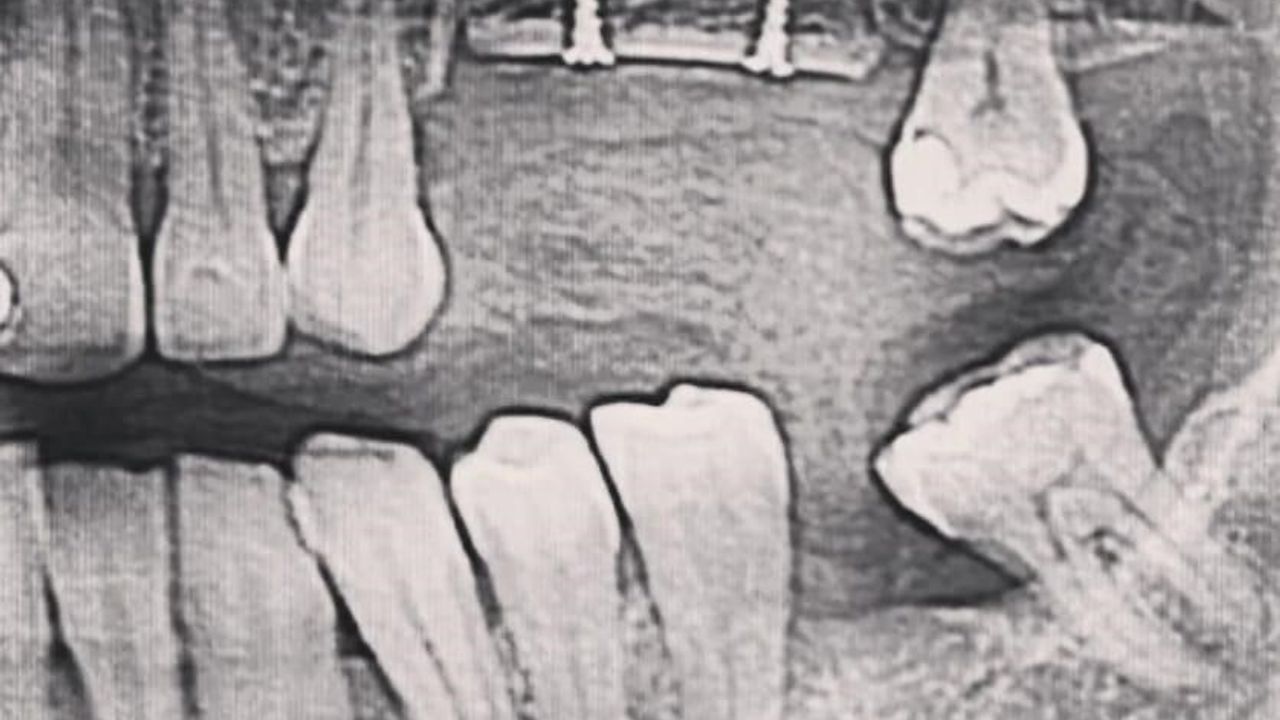

Kemik oluşumu tamamlandıktan sonra ise rutin implant uygulamalarına geçildiğini vurgulayan Özbaylar, sözlerine şöyle devam etti, “Ogmentasyon üst çene yada alt çenede Alveol Kemiği Ogmentasyonu (Genişletme) Diş çekimlerinden sonra, uzun dönemde karşılaşılan en büyük problemlerden biri çene kemiklerinde görülen erimedir. Diş kayıplarının tedavisi, implant uygulamaları ile giderilecekse kemik yüksekliği ve hacmi daha da önem kazanır. Implant uygulaması, belirli yükseklikte ve kalınlıkta kemik varlığını gerektirir. Erken yaşta diş kayıpları ya da yoğun diş eti iltihabı sonucu kemik hacminde oluşan azalmaları kemik onarımları ile giderilebilir. Bu onarımlar, hastaların kendi vücutlarından alınan kemik ile gerçekleştirilebildiği gibi, inorganik materyaller de aynı amaçla uygulanabilir.”

Kemik yetersizliğinin en önemli ve başlıca iki nedeninin diş kayıpları ve periodontal hastalıklar olduğunu hatırlatan Diş Hekimi Dündar Özbaylar, “Bunların yanı sıra travma nedeniyle de diş çevresinde kemik yetersizlikleri görülebilmektedir. Periodontal hastalıkların oluşmasını etkileyen en önemli faktörlerden birinin sigara kullanımı olduğu unutulmamalıdır. Sigara kullanımı, diş eti hastalıklarına ve diş çevresinde yer alan kemiklerin kaybında önemli bir rol oynamaktadır. Birçok çalışma sigara kullanımının ağız içi yapısına önemli oranda zarar verdiğini göstermiştir. Sigara kullanımının yanı sıra kötü beslenme gibi bazı durumlar da kemik kaybı yatkınlığını artırabilmektedir.” şeklinde konuştu.